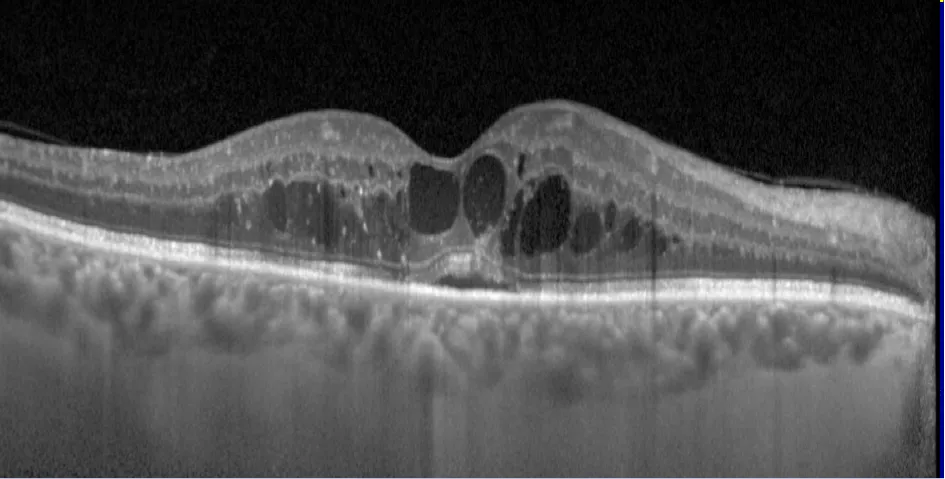

Si le traditionnel fond d'œil nécessitant des heures sous gouttes reste l'examen de référence, sachez qu'au centre, nos rétinographes ultra grand-champ ainsi que les examens en OCT-scan nous épargnent très souvent d'avoir à vous dilater les pupilles, pour un résultat d'imagerie encore plus précis de votre rétine. Concrètement, ça veut dire que pour un simple contrôle annuel sans anomalie détectée, tout va très vite.

L'OCT maculaire au Centre Rabelais →Centre Ophtalmologique Rabelais — 📞 04 78 95 09 08